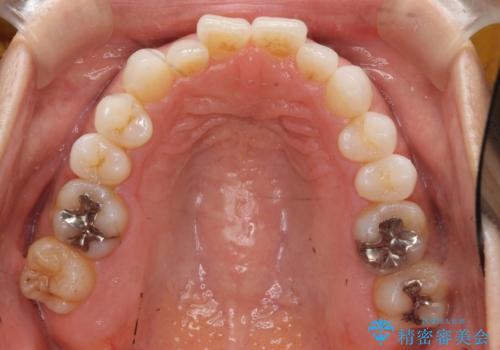

30代女性 前歯のがたつき

- 30代女性

- インビザライン

- 1年5ヶ月

- 前歯のがたつきを主訴に来院。

右下の奥の銀歯も治療しています。

- 115.5万円 矯正治療 85万円、奥歯ジルコニアクラウン11万円(ZrCr 10万円、仮歯1万円、矯正用仮歯2万円)セラミックインレー7万円費用は治療当時の料金となります

下の前歯を下げるため、IPR(歯をわずかに削る処置)を行っています。